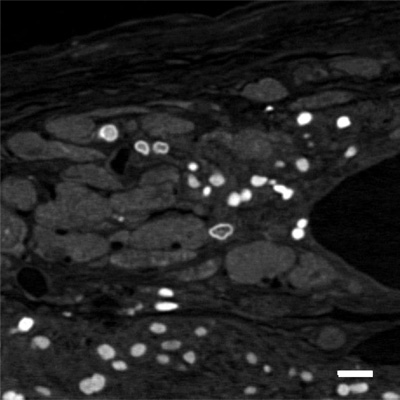

APEX2在來(lái)自健康人的人iPS細(xì)胞的細(xì)胞核中表達(dá),并誘導(dǎo)分化成心肌細(xì)胞。然后,將該iPS細(xì)胞衍生的心肌細(xì)胞移植到模型心肌梗塞模型小鼠中。移植后6個(gè)月,用X射線顯微鏡觀察顯示移植的心肌細(xì)胞的細(xì)胞核是白色的并且成功地可視化三維排列(圖1)。

圖1.心肌細(xì)胞移植后6個(gè)月的X射線顯微鏡圖像

(左)APEX 2將移植細(xì)胞的細(xì)胞核顯示為白色。

(比例尺:20μm)